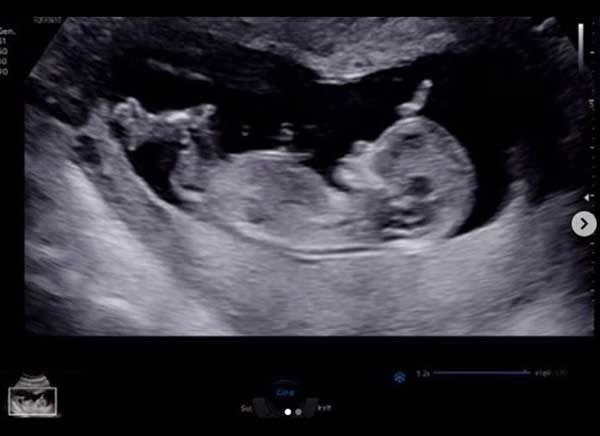

앞서 지난 5일 김영은은 자신의 인스타그램에 "골든이는 아...들배가 뭉쳐서 1주일 만에 다시 찾은 병원. 이 녀석 엄마한테 너의 존재감을 알리려고 그런거니? 왠지 아빠 판박이로 태어날 거 같구나 다들 딸로 알고 계셔서 잘못된 정보 정정합니다♀️ #16주#황금돼지맘#아들#뱃속에서부터#밀당하네#짜시기#아빠가자길닮았나보다고하던데#골든아빠화이팅#내일도승리하세요무적✌"라는 글과 함께 초음파 사진을 올려 누리꾼들의 이목을 모은 바 있다.